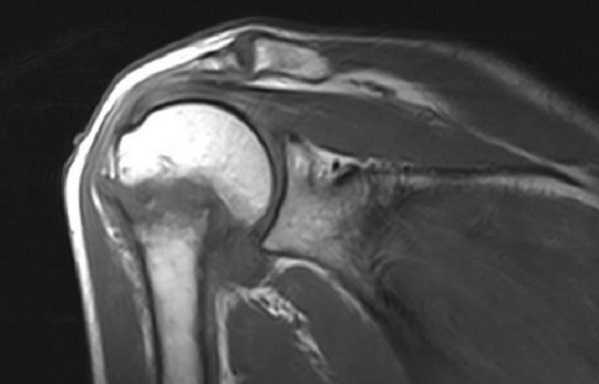

МРТ плечевого сустава в корональной плоскости. Отмечается вколоченный перелом хирургической шейки плечевой кости.

Как правило, МРТ плечевого сустава назначается врачом-ортопедом пациентам для исследования таких состояний, как переломы, дегенеративные изменения, суставные повреждения травматического характера, разрывы вращательной манжеты, травмы рабочего характера (например, связанные с вибрацией), травмы спортивного характера, инфекционные и воспалительные процессы, новообразования в мягких тканях и в костях, отеки, болевой синдром, кровотечения вокруг сустава и в мягких тканях, уменьшения возможности движения плеча.